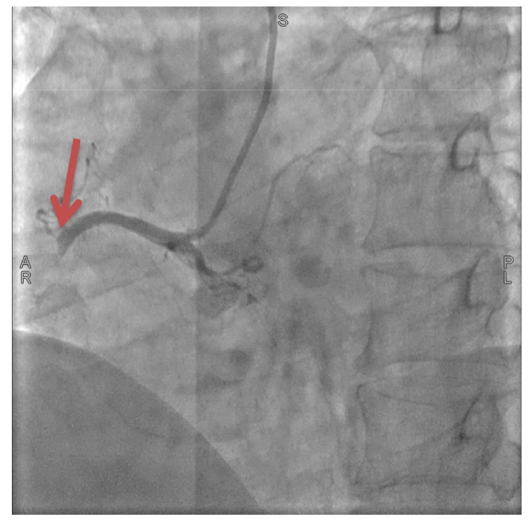

闭塞的右冠状动脉。

一场与时间的赛跑随即展开,泰康同济胸痛中心立即启动急性心肌梗死救治绿色通道,急诊冠状动脉造影显示郑先生右冠状动脉完全闭塞。从进入医院大门到手术器械成功开通堵塞血管仅用时51分钟,远低于国际公认的90分钟黄金标准。术后郑先生胸痛症状迅速缓解,生命体征逐渐平稳,目前已转入普通病房观察。